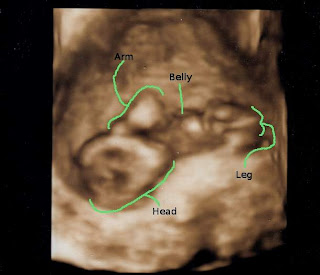

Ultrasound Pics!!!

Heart beat: 154

Baby's Measurements: 5.5 cm

Cervical Length: 3.9 (yay!)

The guy even did a 3D one!!!

And I didn't even ask :)